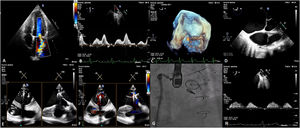

A 50-year-old patient with a history of complex congenital heart disease with multiple reoperations including mechanical aortic valve replacement and bioprosthetic pulmonary valve replacement complicated by endocarditis, underwent percutaneous mitral valve (MV) repair (MVR) due to severe symptomatic mitral regurgitation (MR) caused by anterior leaflet prolapse in a dysplastic valve (Figure 1, panels A and B).

The main difficulty of the procedure was to find adequate echocardiographic views to perform the transeptal puncture and valve grasping, since the usual ones were not feasible given the complexity of the patient's heart disease. The use of three-dimensional tools in real-time enabled an adequate orientation to guide the transseptal puncture and evaluate the distance from the foramen ovale to the valve plane (Figure 1, panels C and D). The catheter guide and mitral grasping were performed from transgastric views (Figure 1, panels E and F), which enabled the successful implantation of an NTr MitraClip system (Abbott Laboratories, AbbottPark, IL, USA) with functional and echocardiographic improvement of the MR, leading to a reduction to grade 2 MVR (Figure 1, panels G and H).